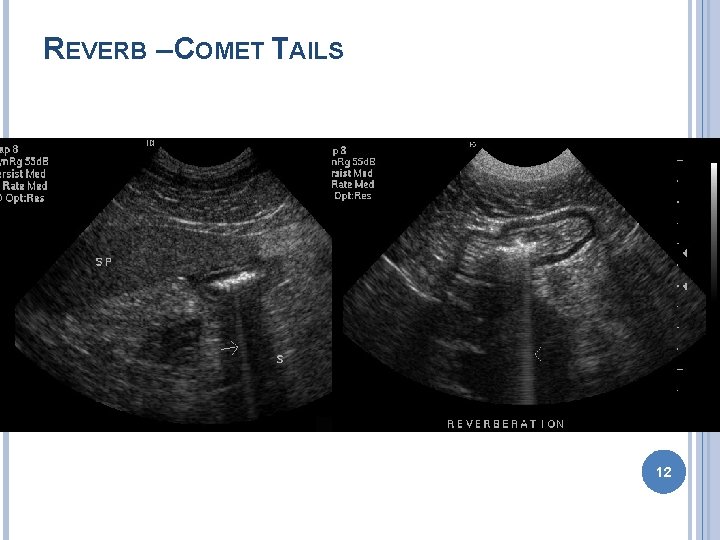

ARTIFACTS Improper machine settings – gain Reverberation � Mirror image – liver GB � Comet tail – gas bubble � Ring down – skin transducer surface Acoustic shadowing Acoustic enhancement Edge enhancement � Border of kidney 11

REVERB – COMET TAILS 12